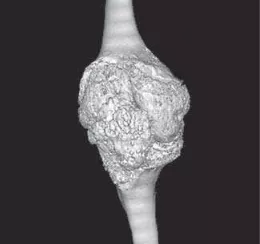

Фото 11. Костные эрозии у девочки с РФ-позитивным полиартикулярным ЮИА [9].

Фото 12 (А, Б). Анкилозы в костях кисти при полиартикулярном ЮИА РФ-позитивном. КТ, 3D-реконструкция: А — тыльная сторона, Б — ладонная сторона. Деформация и нарушение положения костей кисти за счет анкилоза лучезапястного (1), межзапястных (2), II запястно-пястного (3) суставов [4].